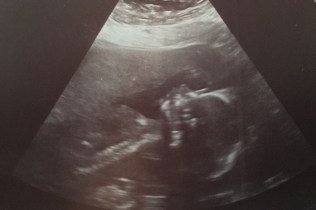

What’s that anatomy ultrasound all about anyway?

The anatomy or morphology ultrasound is a routine ultrasound that occurs between 18 and 22 weeks of pregnancy. At this scan, the ultrasound tech (sonographer) examines the baby from head to toe. Like all routine medical procedures in pregnancy, you can choose whether you want to have this ultrasound or not. Before your ultrasound you will need to drink a lot of water and hold your bladder.

The sonographer looks for specific anomalies and takes measurements to assess whether your baby is growing as expected. If you didn’t have a dating ultrasound, these measurements can help us confirm your due date. They also look at your baby’s umbilical cord to see if it has the typical 2 arteries and 1 vein. Some babies have just 1 artery and 1 vein.

The sonographer will look to see where your placenta is, and how close it is to your cervix. The sonographer also looks at how much amniotic fluid is around your baby.